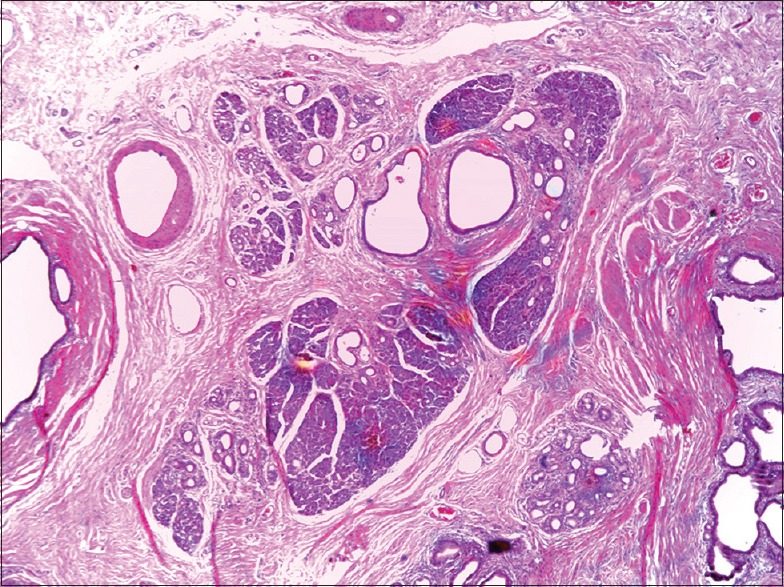

Ectopic Pancreas Causing Partial Gastric Outlet Obstruction: A Case Report and Review of Literature.

Ectopic pancreas is a rare cause of gastric outlet obstruction, perhaps rarer still among Africans. Although the entity is known, the diagnostic challenges are enormous, especially in the poor-resource environment. Gastric outlet obstruction resulting from ectopic pancreas in an adult is the first of its kind in our center; we, therefore, present this case to describe the challenges faced with diagnosis, treatment, and the lesson learned. Ectopic pancreas should be considered in the differential diagnosis of gastric outlet obstruction.